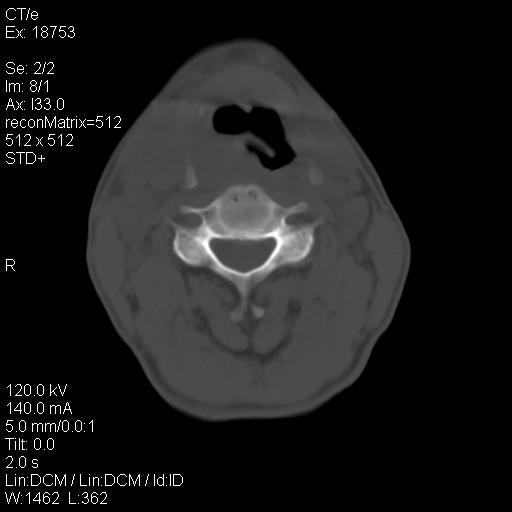

标题: CT21693:男 58岁 右侧咽部疼她2天余 PE:右侧扁桃体肿大 压痛 [打印本页]

标题: CT21693:男 58岁 右侧咽部疼她2天余 PE:右侧扁桃体肿大 压痛

右化脓性扁桃体炎症伴咽后壁脓肿形成.